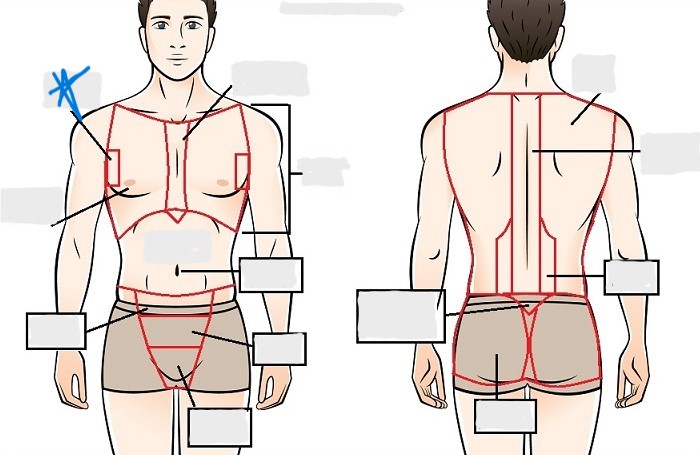

axial

cephalic

occipital

frontal

otic

orbital

nasal

oral

mental

cervical

dorsal

scapular

vertebral

lumbar

sacral

gluteal

thoracic

sternal

mammary

axillary

abdominal

umbilical

pelvic

inguinal

pubic

perineal

appendicular

acromial

brachial

antecubital

olecranal

antebrachial

carpal

manus

coxal

femoral

patellar

popliteal

crural

sural

peroneal

calcaneal

plantar